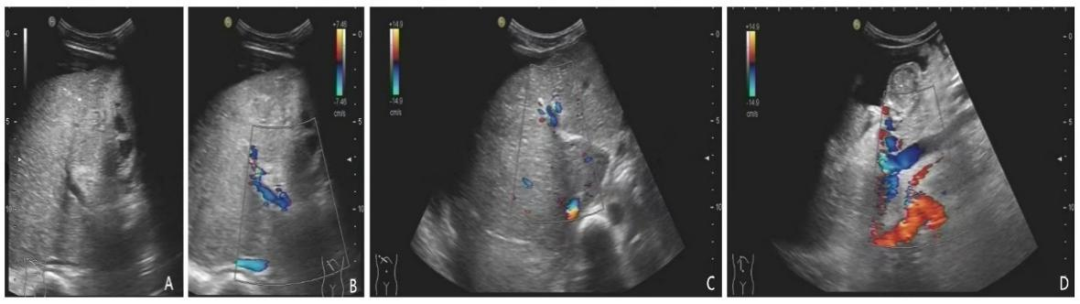

- Cell Rep Med:肠道准备可促进肠道内病原体定植和易位并加重炎症 本研究旨在探讨结肠镜检查前的肠道准备对肠道微生物群与肠道微环境的作用,并阐明在IBD背景下肠道准备对疾病发展的影响。……